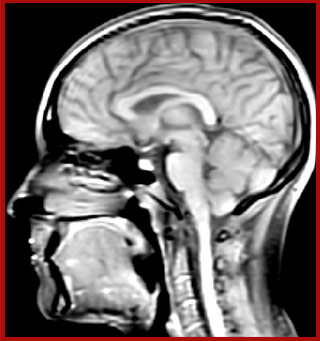

of limiting MWI to the brain, even without the cerebellum, we can now spend about the same amount of time and scan the whole brain and the cervical spinal cord, which is a huge boost for us.” Dr. Rauscher says, “For MWI we perform 3D T2 with 32 or more echoes. This used to take a long time, but with Compressed SENSE we can decrease this to ten minutes for the whole head. Because of the large field of view (FOV) on the readout direction, we even get information from the brainstem, which we previously missed when we were using the GRASE approach. Having the whole head scan is nice because it has spatial resolution, orientation and FOV that are comparable to the standard 3D clinical MS scans, including the FLAIR and 3D T2, and a 3D T1 for brain volume.”

T1 - Weighted, Myelin Water Fraction Superimposed

Spinal cord coverage

Smaller, more isotropic voxels

Excellent detail in quantitative maps

Images courtesy of Adam Dvorak, Department of Physics and Astronomy, University of British Columbia